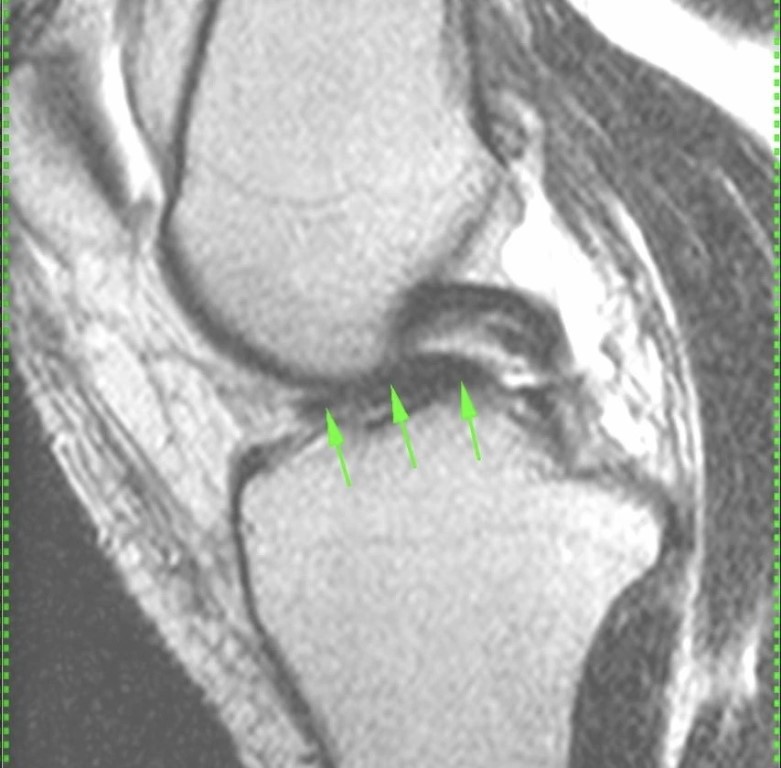

Фото Хоть и однотесловик, но ручку лейки (ведра) видно замечательно! Напомним, что разрыв мениска по типу #ручкалейки/ведра (#buckethandletear) представляет собою отрыв свободного суставного края мениска от его основания (капсулярного края), которое/который прикреплено/прикреплен к бедренной и большеберцовой костям связками и смещение этого оторванного края внутрь сустава, так, что мениск вместо полумесяца 🌙 начинает собою представлять что-то типа буквы ⭕ По классификации разрыв такой относится к продольным (потому что капсулярный полукруглый край мениска считается, типа, продольной осью мениска почему-то и поэтому разрывы, параллельные этому краю, называются продольными вертикальными, в отличие от поперечных (которые пересекают мениск от суставного края до капсулярного) и продольных горизонтальных, которые похожи на птичий клюв, но не попугая (это особый тип разрыва мениска, кривой, как турецкая сабля клюв попугая).